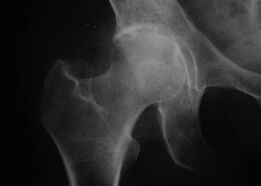

Wygląd stawu z artrozą

Koksatroza, artroza stawu biodrowego

W przypadku tej choroby obserwuje się klasyczny obraz kliniczny artrozy.

Pierwszym objawem koksartrozy jest dyskomfort w stawie biodrowym po wysiłku fizycznym.

W przypadku postępującej choroby zwyrodnieniowej stawów nasilają się bóle, pojawia się sztywność i ograniczona ruchliwość.

Pacjenci z ciężką postacią choroby zwyrodnieniowej stawów oszczędzają chorą kończynę, unikając nadepnięcia na nią, a podczas postoju wybierają pozycje, w których ból jest najmniej odczuwalny.